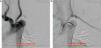

She remained asymptomatic until around a month later, when she was readmitted twice in 15 days for acute hypertensive pulmonary edema. Laboratory tests revealed deterioration of renal function but inflammatory parameters were still normal. Stress echocardiography showed no wall motion abnormalities; given the suspicion of renal involvement of the vasculitis in view of persistent severe renal dysfunction despite optimization of blood volume and suspension of nephrotoxic medication, abdominal Doppler ultrasound was repeated. This showed the abdominal aorta with irregularly thickened walls but normal flow and stenotic lesions with marked hemodynamic repercussions at the origin of the superior mesenteric artery and left renal artery. Abdominal CT angiography confirmed the presence of a thin sheath of tissue surrounding the abdominal aorta, causing significant preocclusive stenosis of both renal arteries and the superior mesenteric aorta (Figure 3). Stenoses of around 50% were also detected in the inferior mesenteric artery and the celiac trunk.

Given the obvious progression of the disease under corticoid therapy, treatment with cyclophosphamide pulses was begun and angioplasty of the renal arteries and celiac trunk was performed, with a good angiographic result and complete recovery of renal function. The patient has remained under corticoid therapy, without further complications or evidence of disease progression in other arterial territories.